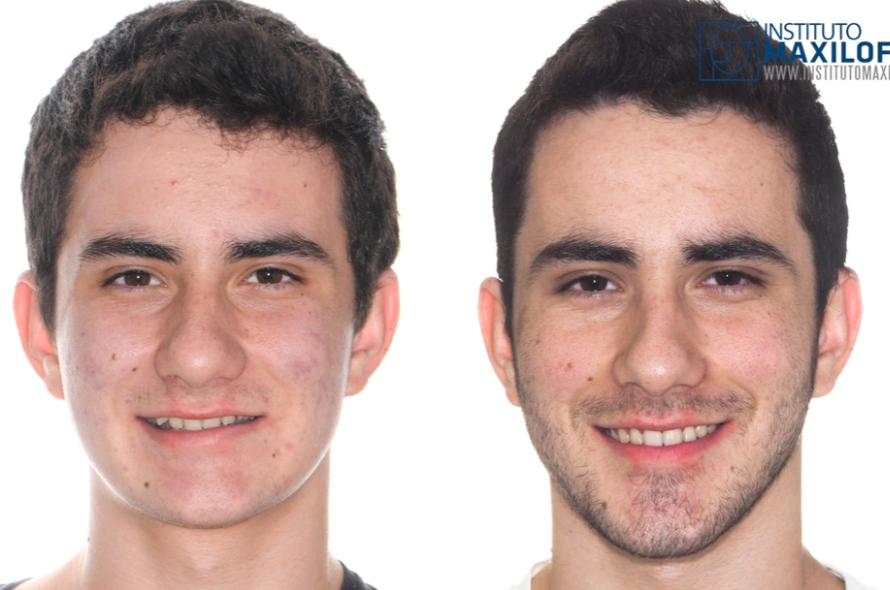

Lets start with gustavo, Alfaro bimax case, the most famous bimax result online:

lets look at his skeleton, which explains the huge transformation:

Lets start with gustavo, Alfaro bimax case, the most famous bimax result online:

lets look at his skeleton, which explains the huge transformation: